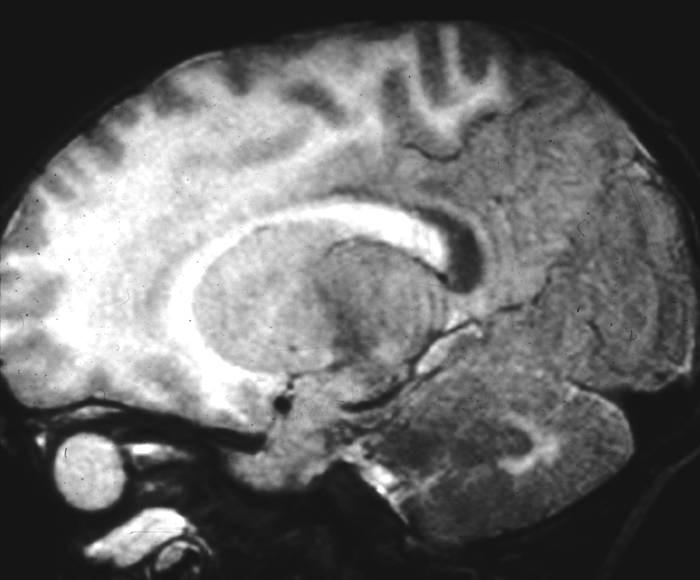

Alexander Disease Alexander Disease

• Frontal predominance, U-fibers involved early Frontal predominance, U-fibers involved early

• Basal ganglia and thalami often involved Basal ganglia and thalami often involved

• Enhancement near frontal horns Enhancement near frontal horns

JA Phelan and LH Lowe, Univ. of Missouri - KC Barkovich JE. Pediatric Neuroimaging 2005